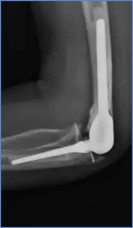

Elbow Joint implants

Standard Specification for Total Elbow Prostheses

ASTM F2887: Standard Specification for Total Elbow Prostheses.

Elbow Implant Requirements

ISO 21534:Non-active Surgical Implants- Joint replacement

Implants- Particular Requirements.